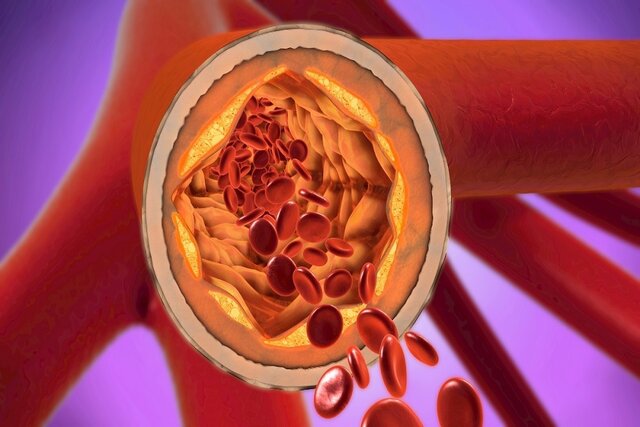

چرا التهاب در بیماری قلبی اهمیت دارد؟ التهاب نقش حیاتی در هر مرحله از توسعه و تجمع پلاک چربی در شریانها دارد که باعث ایجاد وضعیتی به نام «تصلب شرایین» میشود که میتواند منجر به حملات قلبی و سکته مغزی شود.

از لحظهای که یک رگ خونی آسیب میبیند، چه از قند خون بالا و چه از دود سیگار، سلولهای ایمنی بلافاصله به آن ناحیه نفوذ میکنند. این سلولهای ایمنی متعاقباً ذرات کلسترول را که معمولاً در جریان خون شناور هستند، میبلعند تا یک پلاک چربی تشکیل دهند که در دیواره رگ قرار میگیرد.

این فرآیند برای دههها ادامه مییابد تا اینکه سرانجام یک روز، واسطههای ایمنی، کلاهکی را که پلاک را احاطه کرده است، پاره میکنند. این امر باعث تشکیل لخته خونی میشود که جریان خون را مسدود میکند، بافتهای اطراف را از اکسیژن محروم میکند و در نهایت باعث حمله قلبی یا سکته مغزی میشود.

از این رو، کلسترول تنها بخشی از داستان است. در واقع، این سیستم ایمنی است که هر مرحله از فرآیندهایی را که باعث بیماری قلبی میشوند، تسهیل میکند.